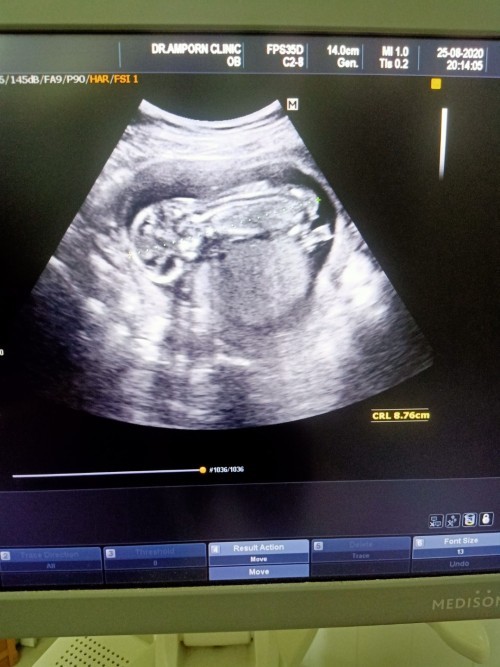

แม่ๆคนไหนมีภาพอัลตร้าซาวด์ประมาณ13วีคบ้างคะ ของเรา13วีค ภาพแบบนี้ค่ะ ดูไม่ออกเลย?

13week. จ้า❤

13วีคจ้า

13weeksคร้า

13 week ค่ะ

13วิคคะ